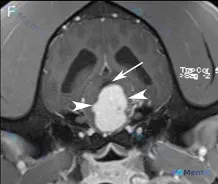

这是一张脑部横断面增强后 T1WI 图像:

- 可见一较大的显著强化髓内占位,使脑干扩张;

- 病灶周围有水肿;

- 中脑导水管被背侧推挤并受压;

- 侧脑室轻度不对称扩张。